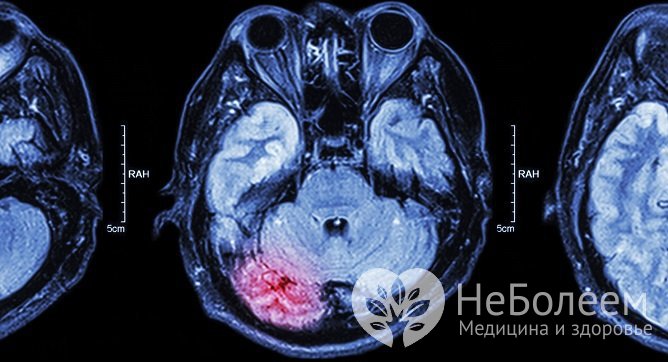

Прогноз при ишемическом инсульте головного мозга определяется тяжестью заболевания, эффективностью и своевременностью лечебных мероприятий и резервными возможностями организма.

В соответствии со статистическими данными, наиболее высокая летальность при ишемическом инсульте отмечается в первый месяц – 15–25% пациентов погибает, из них 40% – в первые двое суток после атаки. К концу первого года выживает 60-70% пациентов, в течение пяти лет – 50%, спустя 10 лет – 25%. Рецидив инсульта в течение пяти лет происходит у 30% пациентов.

Ишемический инсульт вызывается блокированием кровотока в одной из мозговых артерийНеврологические нарушения, приводящие к инвалидности, в течение первого месяца после перенесенного инсульта отмечаются у 60-70% пациентов, спустя полгода – у 40%, спустя год – у 30%. Лучшая динамика реабилитации наблюдается в первые три месяца. Если нарушенные функции не удалось восстановить в течение года, в дальнейшем их восстановление маловероятно.